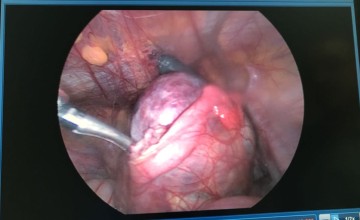

أجرى فريق جراحة الصدر في المدينة الطبية بجامعة الملك سعود، عملية استئصال دقيقة لورم مُنتشر في الغشاء البلوري المغطي للجهة اليمنى من التجويف الصدري والرئة عن طريق الروبوت مع استخدام العلاج الكيميائي المسخن، وذلك لمريض خمسيني يعاني من ورم غير حميد في الغشاء البلوري للصدر.

وأوضح استشاري جراحة الصدر بالمدينة الطبية الدكتور صالح عبدالرحمن الناصر أن هذا النوع من العمليات باستخدام العلاج الكيميائي المسخن يُعد من العمليات النوعية على مستوى المملكة والمعقّدة جدًا في جراحة الأورام بالنسبة للتجويف الصدري التي تتطلب كفاءات عالية من ناحية التدريب والخبرة، حيث تم استئصال الورم المُنتشر عن طريق تقشير الغشاء البلوري المغطى لجدار الصدر، وكذلك الغشاء المغطى للرئة والحجاب الحاجز وغشاء التامور، ومن ثم استخدام العلاج الكيمائي المسخن داخل تجويف الصدر بدرجة حرارة 42 درجة مما يساعد في ضمان استئصال الورم بنسبة عالية وتقليل احتمال عودتها مجددًا.

وأكد الدكتور الناصر أن استخدام الروبوت يأتي كعامل مساعد في الوصول لمناطق يصعب الوصول إليها عن طريق الشق الجراحي الاعتيادي، مُعربًا عن شكره وتقديره للفريق الطبي المشارك.